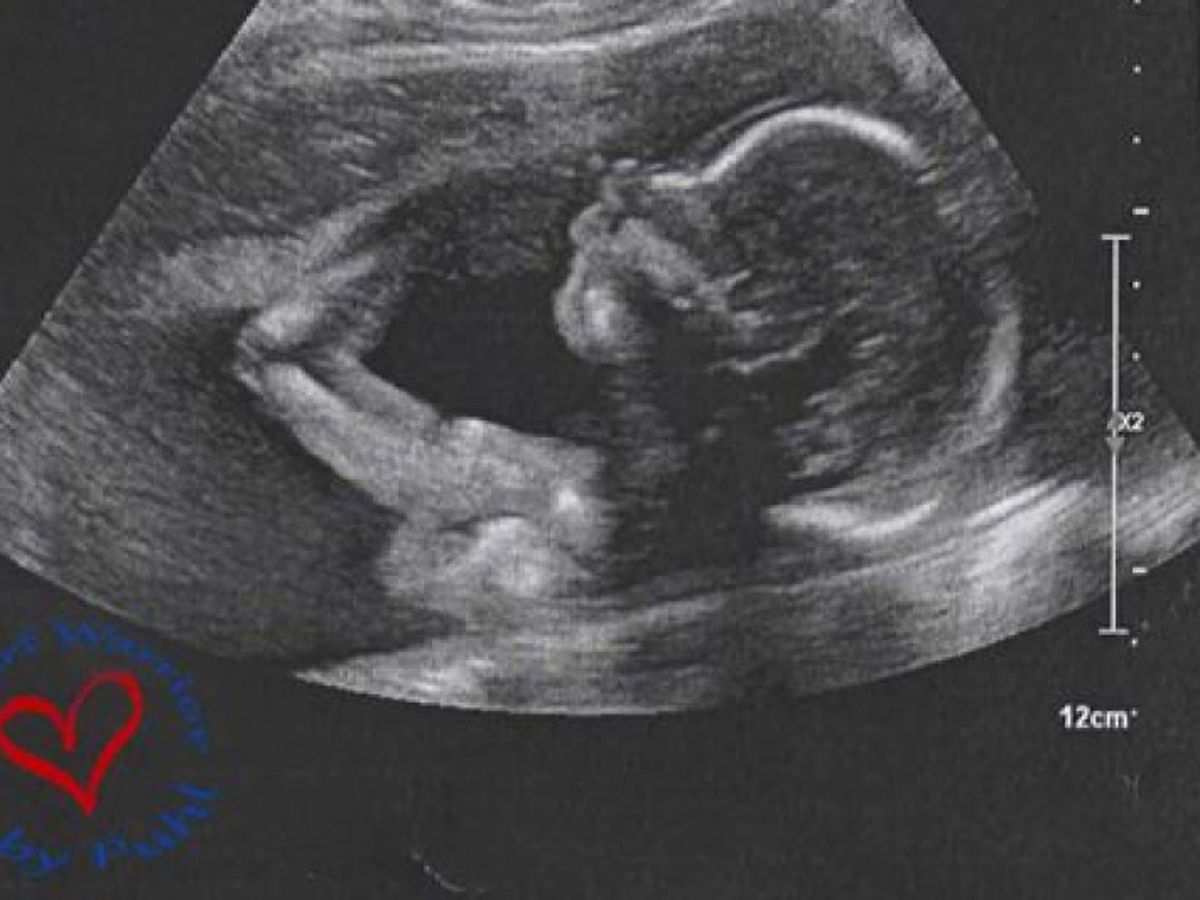

Baby Puhl's HLHS Fundraiser

At my 20 week anatomy scan we found out our son was diagnosed with a rare congential heart disease called Hypoplastic Left Heart Syndrome, its an incurable deadly disease that can be fatal without the correct surgeries he will need to recieve within days of being born.